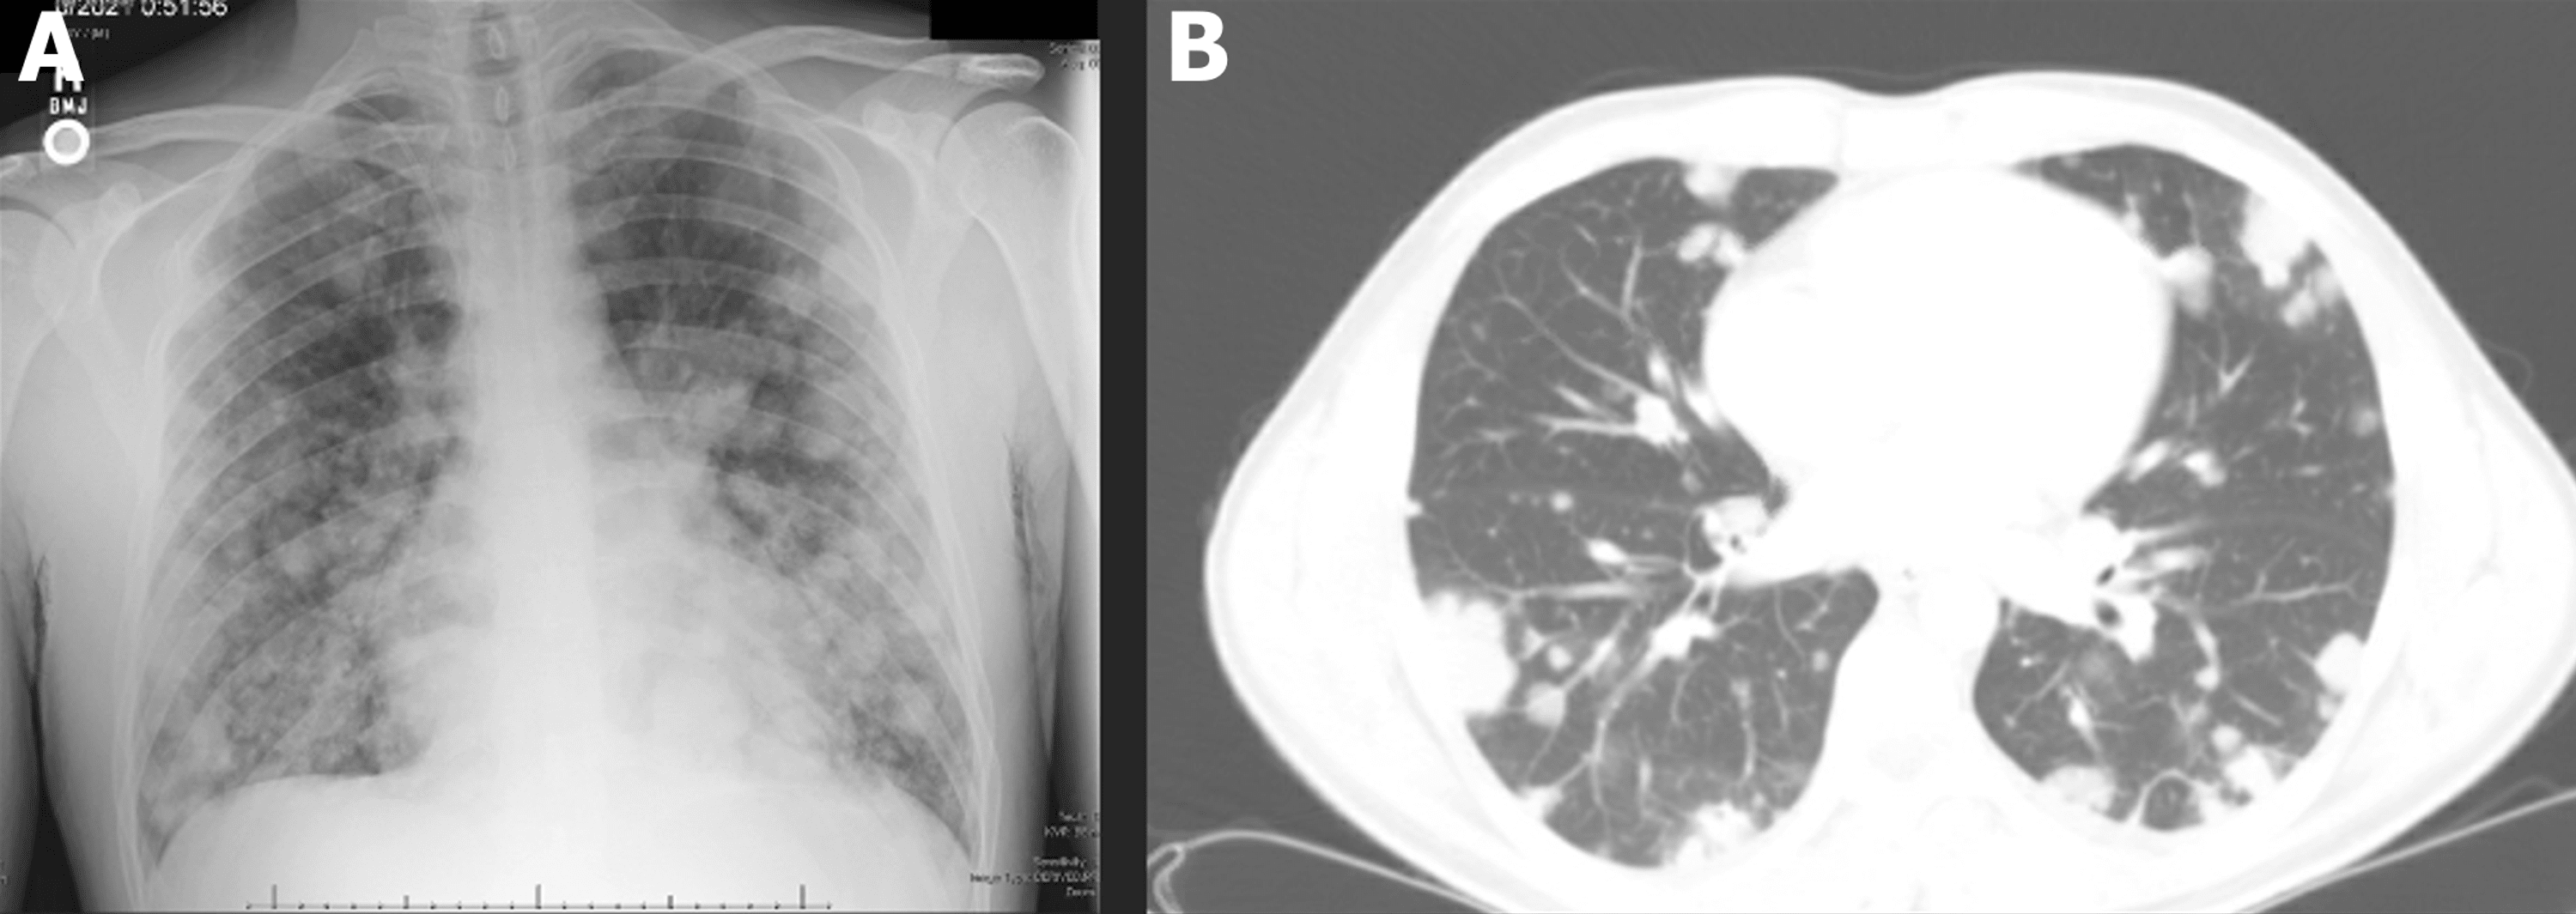

A UNIQUE PRESENTATION OF METASTATIC TESTICULAR CANCER IN A YOUNG MALE Testicular Cancer Brain Metastases Symptoms 1 most cases with brain. Our study evaluated the incidence, imaging characteristics, and prognosis of brain metastases originating. signs and symptoms of testicular cancer include: testicular cancer with neurological symptoms indicates brain metastases. A lump or swelling in either testicle; Signs and symptoms caused by brain metastases can vary based on the location, size and rate of growth. Testicular Cancer Brain Metastases Symptoms.

Cancer metastasis causes, symptoms and metastasis survival rate Testicular Cancer Brain Metastases Symptoms signs and symptoms of testicular cancer include: Signs and symptoms caused by brain metastases can vary based on the location, size and rate of growth of the metastatic. Our study evaluated the incidence, imaging characteristics, and prognosis of brain metastases originating. A feeling of heaviness in. common treatments for brain metastases from testicular primary cancers include surgical resection,. Testicular Cancer Brain Metastases Symptoms.